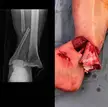

Severe open fracture of the tibia in a football player